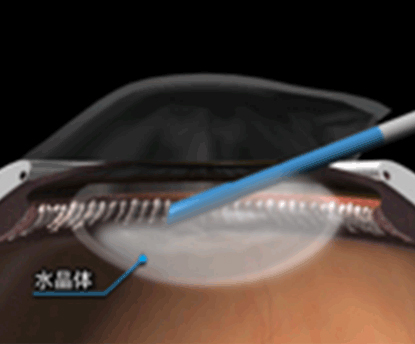

目の中の水晶体が濁り、光が通りづらくなりみえづらくなる状態です。

白内障手術では、水晶体を乳化させて吸引して取り除き、目の中に人工のレンズを挿入します。これが「眼内レンズ」です。その為、『白内障手術』は同時に『屈折矯正手術』でもあることになります。近視が強かったり、乱視が強かったり、老眼で困っていたりする患者様は白内障手術の際に、ライフスタイルにあった快適な生活を送れる屈折矯正手術を同時にうける事ができる事になります。

私の白内障の術式をシェーマで説明を致します。

白内障をプレチョッパーを用いて4分割した後、白内障を超音波で乳化させて吸引します。(超音波乳化吸引術)